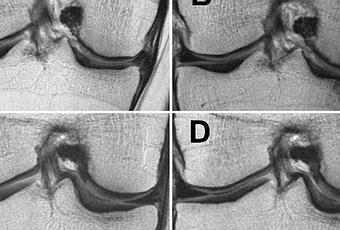

Les chercheurs californiens ont analysé via IRM les différences de dégénérescence de toutes les structures articulaires du genou (ménisques, cartilage articulaire et moelle osseuse) chez 640 patients obèses et en surpoids (IMC>25 kg/m 2 ), dont un groupe " de perte de poids " et un groupe témoin. A l'issue de l'étude, les patients ont été classés en 3 groupes : ceux qui ont perdu plus de 10% de leur poids corporel, ceux qui ont perdu de 5 à 10% de leur poids corporel et un groupe témoin final dont le poids est resté stable.

Perte de poids et réduction de la dégénérescence du cartilage : L'analyse confirme que les participants en surpoids et obèses qui sont parvenus à une perte de poids élevée sur une période de 48 mois ont bénéficié d'un ralentissement significatif de la dégénérescence du cartilage de genou. Précisément,

-les patients avec perte de poids de 5% présentent des taux de dégénérescence du cartilage inférieurs à ceux des participants de poids stable ;

-les patients avec perte de poids de 10% présentent une dégénérescence du cartilage encore ralentie.

-Non seulement la perte de poids ralentit la dégénérescence du cartilage articulaire, mais aussi celle des ménisques, ces coussinets de fibrocartilage en forme de croissant qui protègent l'articulation.

-Les effets les plus manifestes sont relevés chez les participants les plus fortement obèses au départ de l'étude ainsi que chez ceux qui ont perdu le plus de poids.